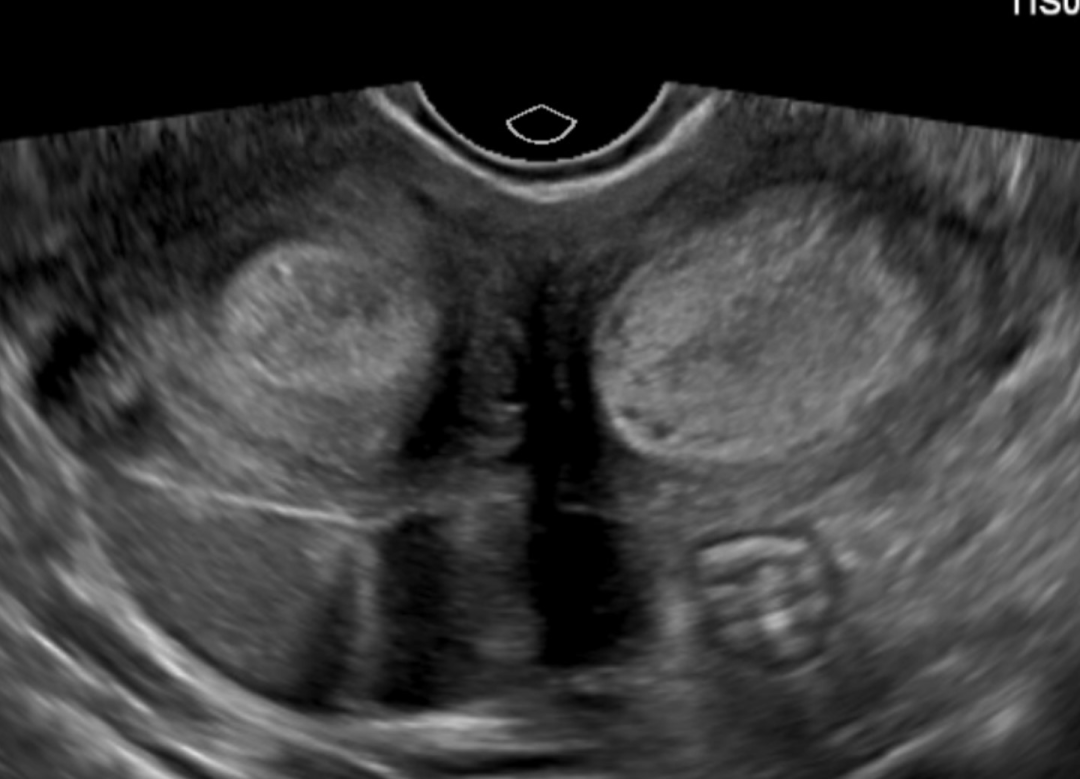

② 经阴道超声:分辨率更高,可清晰显示子宫内腔、宫颈及阴道情况,便于发现双宫腔、双宫颈或纵行阴道隔。

超声典型表现包括:两个不相通的宫腔、分离的子宫体、明显的子宫底切迹以及可能存在的双宫颈等。